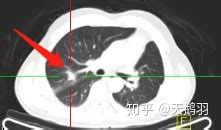

病情分析: 68岁男性,肺部多发性占位 意见建议:你好!肺结节和肺癌在影像学上均为结节状阴影,但是单纯的结节周围光滑,无侵蚀装,如果为炎性的结节在胸片上甚至能看到结节内的液平,以及结节周围炎性水肿带。而肺癌结节常可见于毛刺状,多为单发。靠近肺门位置。结节和肺癌占位有时在影像血上无法完全辨别,还可以行痰找肿瘤细胞,甚至穿刺活检才能确诊

本人是三甲医院资深放射科医生,帮你解释一下。 根据胸部CT的描述来看,考虑继发型肺结核之纤维灶和增殖结节。“右肺上,下叶条索状阴影”这就是纤维灶,至于中叶的微小结节,根据用同一疾病解释的原则,考虑增殖结节。对于肺内的结节,尤其是孤立小结节,诊断很困难,结合纤维灶,考虑肺结核之增殖结节,这是惯例。对于你母亲这种情况,目前没有更好的确诊方法,复查胸部CT是必要的,如果没有任何症状,可以在3月后在同一医院复查胸部CT,如果出现咳嗽、咳血、胸痛等其中任何症状,需要及时就诊。你提供的实验室检查结果对于肺内病灶的诊断没有帮助。另外,胸部CT的射线剂量的确远大于常规胸片,但还是安全的,不必考虑辐射问题。实际上老百姓夸大了射线的危害性。 作过胸部CT为什么又去作胸透?胸透在很多地方已经被淘汰不用了,对你母亲这种情况,胸透没有一分钱的作用。查血的结果与肺内病灶风马牛不相及。 肺结核是完全可能不通过抗结核治疗自己好的,实际上肺内和肺门的钙化点,大多数都是感染结核杆菌的结果。这没有什么奇怪的。